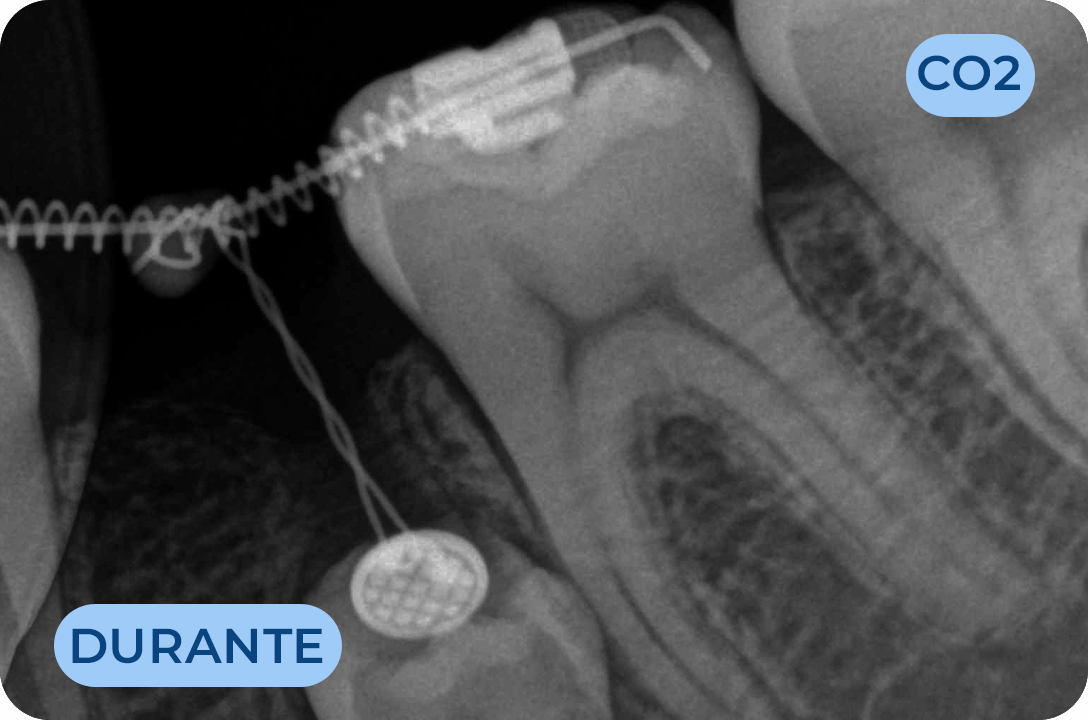

Ortodontia

É a especialidade da Medicina Dentária que se debruça sobre o estudo e correção das más posições dentárias e dos maxilares. Atualmente é possível tratar pacientes de todas as idades, no entanto a 1ª consulta deve ser realizada ainda na infância para intercetar eventuais problemas de desenvolvimento esquelético e funcional.